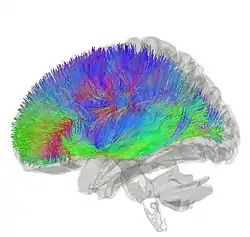

![]() Tractography showing corticostriatal connections | |

[31] The largest connection is from the cortex, in terms of cell axons. Many parts of the neocortex innervate the dorsal striatum. The cortical pyramidal neurons projecting to the striatum are located in layers II-VI, with the most dense projections come from layer V.[32] They end mainly on the dendritic spines of the spiny neurons. They are glutamatergic, exciting striatal neurons.